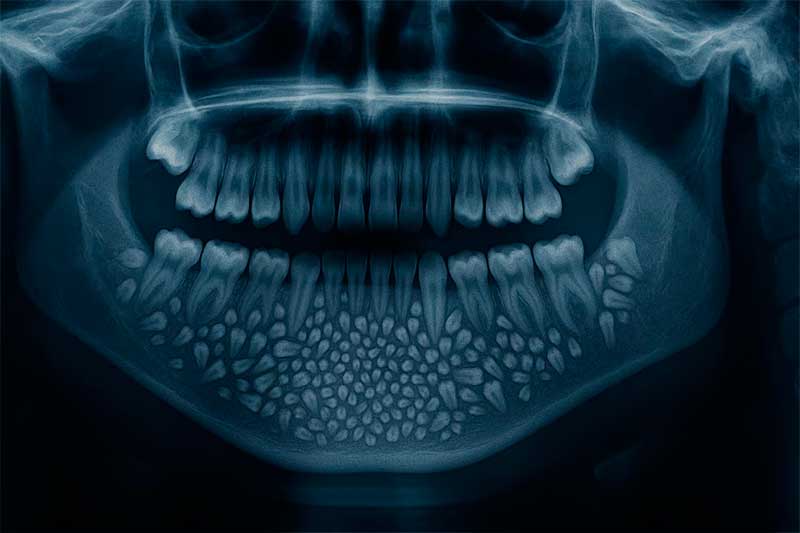

Las radiografías y tomografías computerizadas revelaron la presencia de una masa de aproximadamente 200 gramos alojada en el interior de la mandíbula. El Dr. Senthilnathan, responsable del Departamento de Cirugía Oral y Maxilofacial, identificó la anomalía como un “odontoma compuesto”, una variante benigna de tumor directamente relacionada con el desarrollo dental.

“La especie de tumor que detectamos impidió el crecimiento permanente de los molares en el niño en el lado afectado”, explicó el cirujano tras completar la operación. Las imágenes médicas mostraban numerosos dientes rudimentarios agrupados en un tejido con forma de bolsa, una presentación clínica poco frecuente en la literatura especializada.

La magnitud del descubrimiento sorprendió incluso a los médicos más experimentados. Según informó Science Alert, la bolsa contenía 526 pequeños dientes de dimensiones variables, desde apenas 0,1 milímetros hasta 15 milímetros de longitud. El proceso de clasificación y contabilización de cada pieza dental requirió cinco horas adicionales de trabajo meticuloso en el laboratorio.

La Dra. Pratibha Ramani, directora del Departamento de Patología Oral y Maxilofacial, destacó que todos los dientes extraídos presentaban las estructuras características de las piezas dentales normales: corona, raíz y recubrimiento de esmalte. “Incluso la pieza más pequeña tenía las características de un diente tradicional”, subrayó la especialista, quien enfatizó la ausencia de precedentes con tal número de dientes en los registros médicos mundiales.